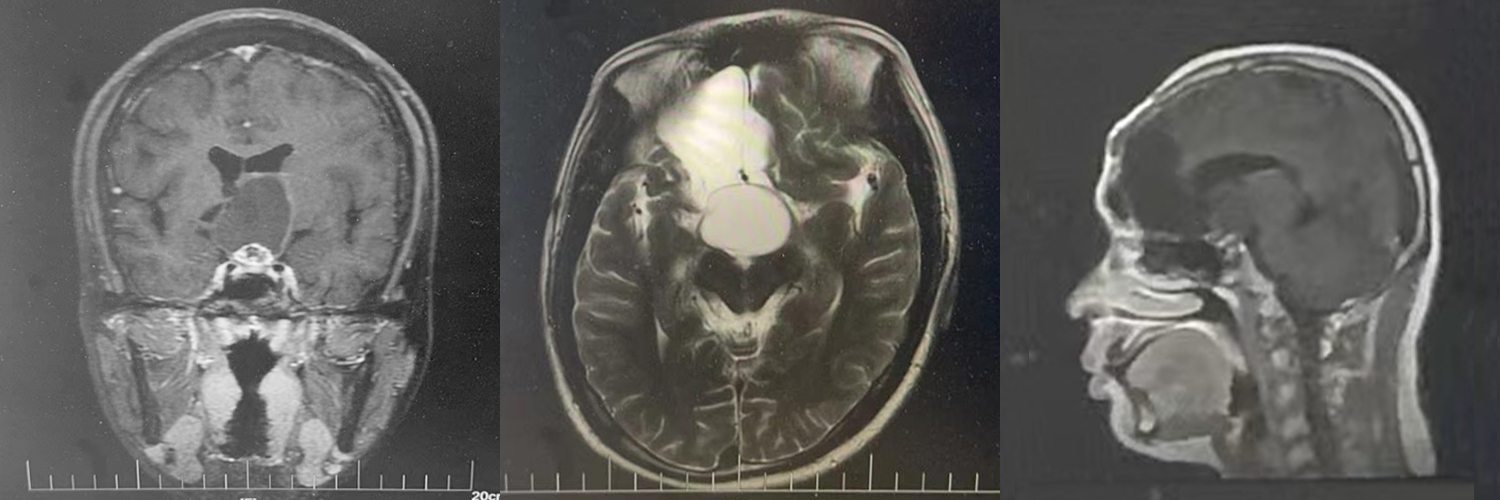

F,24歲

右額顳開顱顱咽管瘤切除術后2年,視力下降3個月,視力右眼0.08,左眼視力眼前20cm數指

MRI:額顳開顱顱咽管瘤切除術后狀態;右額軟化灶;鞍上囊實性占位

診斷:復發顱咽管瘤